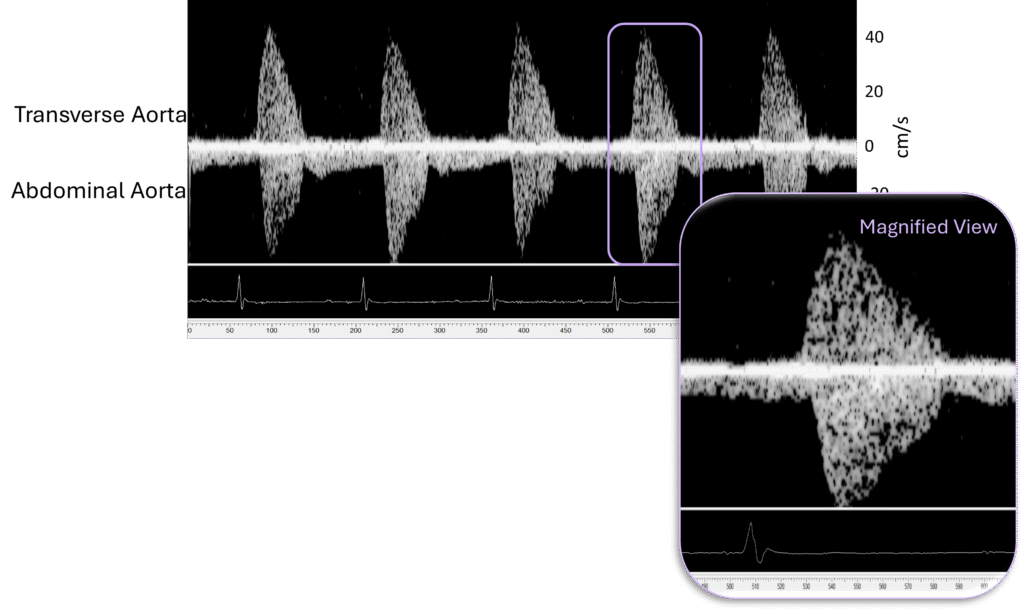

- With dual-probe imaging, the DFVS allows simultaneous measurement at two vascular sites of interest in real-time, ensuring integrated and accurate vascular stiffness pulse wave velocity measurements.

- Flow velocity routinely measured from aortic arch, abdominal aorta, carotid artery, and/or femoral artery

Pulse Wave Wave Velocity